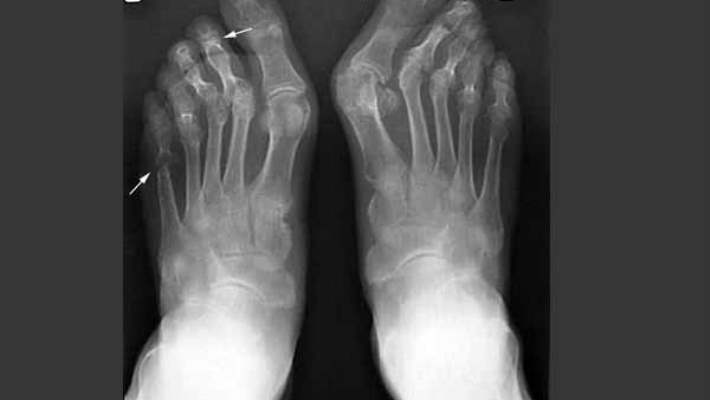

- Gut hastalığı

- Osteoartrit (kireçlenme)

- Romatoid artrit

Teşhis

Aşağıdaki durumlarda bir röntgen filmi çektirebilirsiniz:- Ayağınızın üzerine ağırlığınızı veremiyorsanız

- Her bir ayak bileği kemiğinizin ucunda kötücül bir ağrınız varsa

- Yaralanan yerde kızarıklık, ateş ve hassasiyet gibi enfeksiyon belirtileri varsa veya ateşiniz 37.7 derecenin üzerindeyse

- Şişlik evde uyguladığınız tedaviden iki veya üç gün sonra bile düzelmiyorsa

- Küçük çaplı bir ağrı haftalar sonra bile geçmemişse

- Sabahları veya hareket ettikten sonra ayak bileğinizde şişlik, sertlik ve ağrı varsa